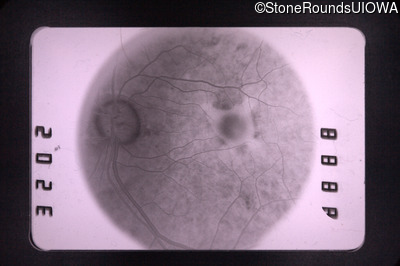

Fluorescein Angiography - Right - 20/50 +1

Exemplar